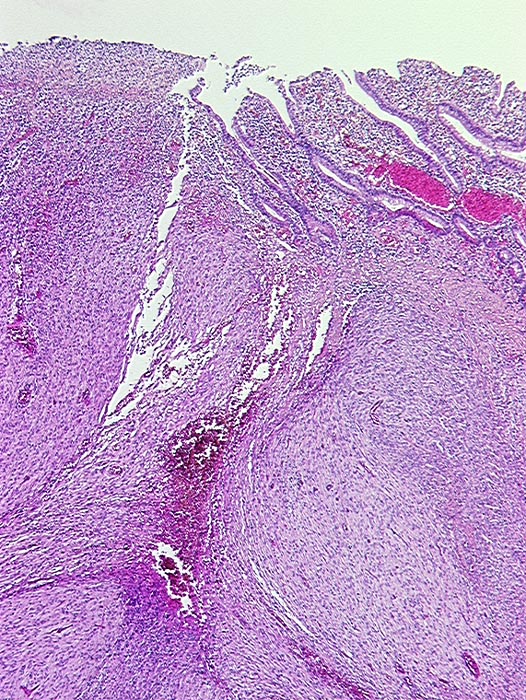

• Scharf begrenzter kugeliger Tumor in der Submukosa des Magenantrums

• Über dem Tumor entzündungsfreie Antrumschleimhaut mit partiell reepithelialisiertem oberflächlichem Ulkus (Quellungsfibrinoid).

• Der Tumor besteht aus längs und quer getroffenen Faszikeln spindelförmiger Tumorzellen, welche an glatte Muskelzellen oder Schwannzellen erinnern.

• Herdförmig pseudozystische Auflockerung des Tumorgewebes.